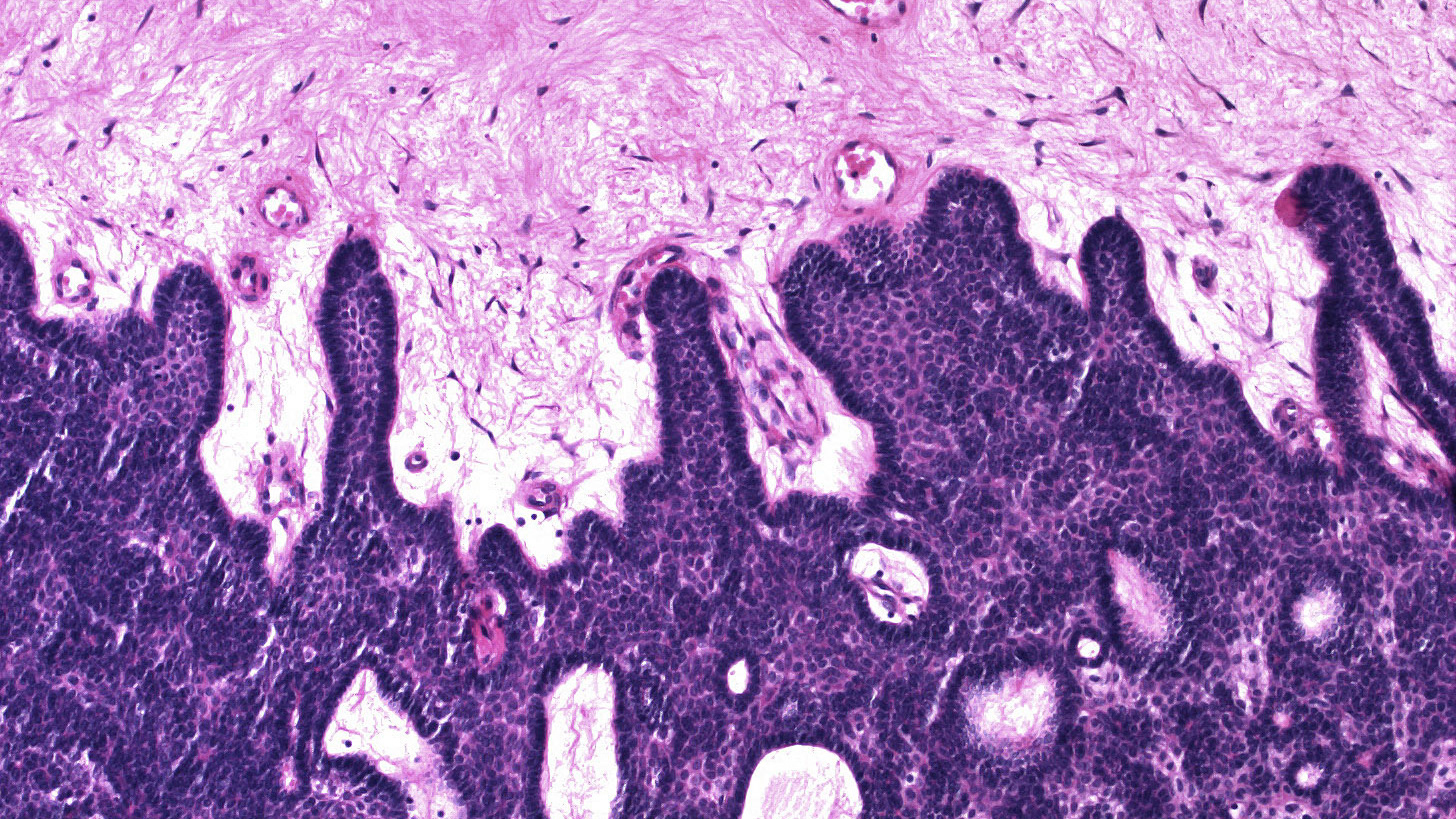

micro | small

2021